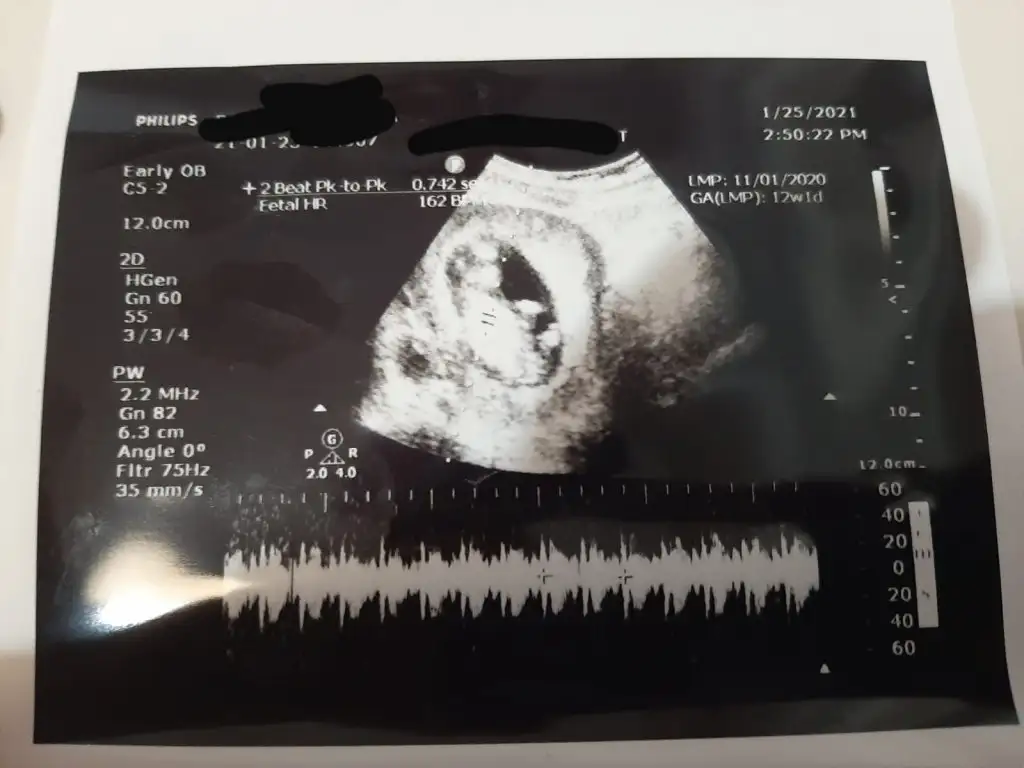

Merhaba Ikra meyra Ikra meyra bana da bakmanız mümkün mü acaba hem 11+3 hem 12+1 haftalık resimleri attım

Eklentiler

• IMG-20210126-WA0014.webp

IMG-20210126-WA0014.webp

26,9 KB · Görüntüleme: 66

• IMG-20210126-WA0013.webp

IMG-20210126-WA0013.webp

18,7 KB · Görüntüleme: 49

• IMG-20210126-WA0012.webp

IMG-20210126-WA0012.webp

26,6 KB · Görüntüleme: 44

• IMG-20210126-WA0011.webp

IMG-20210126-WA0011.webp

17,6 KB · Görüntüleme: 47